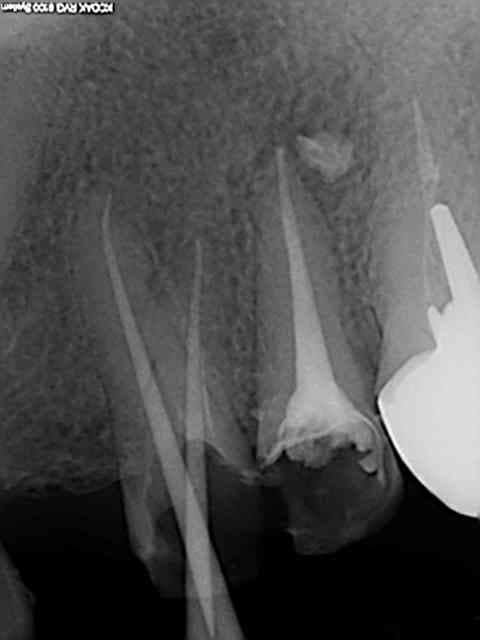

J'utilise le système heroshaper+digue+hypo+condensation

Mac Spadden(thermomécanique)

J'ai posté des radios biopulpectomies et retraitements

canalaires précédemment.

L'obturation 3D est indispensable pour un traitement hermétique.Mon associé utilise le système protaper et

effectivement cela élargit plus.Sur ces 7 dernières années

j'obtiens de bons résultats;mon avis le système heroshaper

casse moins mais n'hésite pas à jeter un heroshaper

même si non déspiralé ;si il a travaillé un peu en force

ou si la morphologie canalaire est un peu compliquée ou courbe;on fait un peu un usage unique pour éviter tout

problème plus tard!(quelque soit le système)on récapitule

avec un instrument à mains;pour une bonne herméticité

le système Mac spadden est le plus efficace ,utlisé par des endos exclusifs,et le moins cher (un cone de gutta est suffisant)Ma séquence classique instrument à main N10

héroshaper N20 6%/4% N25 4% N30 4% MAC SPADDEN un cone de gutta/ciment sealite régular

J'ai reposté quelques radios de biopulpectomies

RTE dans un précédent post...